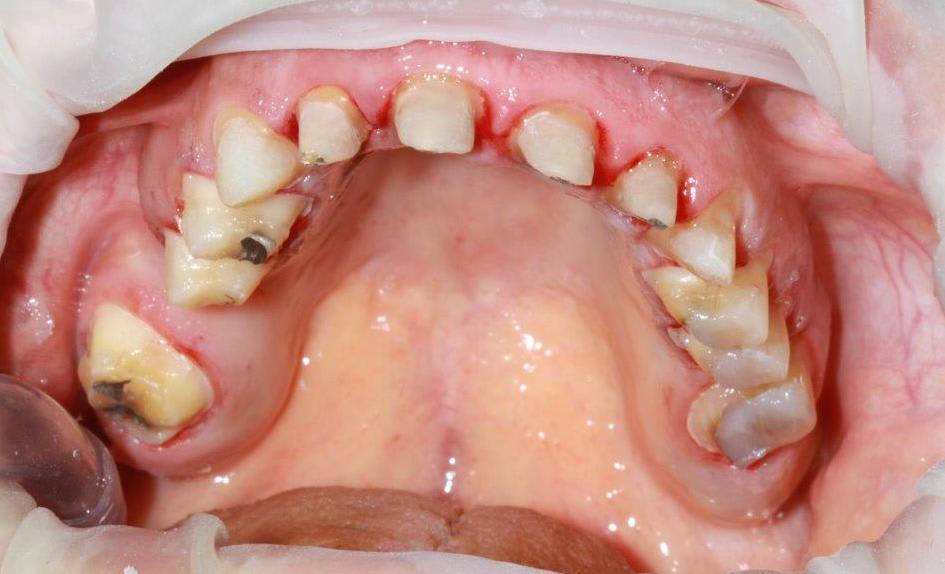

la patiente fume pas mais comme elle joue au bridge peut être fumerait-elle des dunhill.... nan je la soupçonne plutot de dormir la bouche ouverte.

donc possible assechement des dents...

ses coiffes: on a tout essayé.... chappe or jaune+facette resine en haut à gauche, coiffes zircone en bas, coiffes peek sur implants en haut à droite....

donc pas de ccm malheureuse elles auraient pas tenu 6 mois!

--

On a toujours le choix mais entre quoi et quoi?

Vas-y boulégue et l'avenir te le dira!